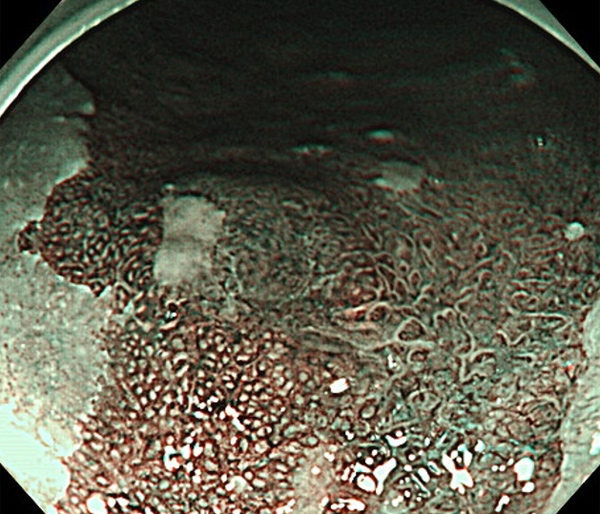

内視鏡所見と病理組織像の1対1対応が可能な症例を公募いたします。主にLSBEに発生した早期癌(HGDを含む)を対象としますが、興味深い症例であればSSBE癌でも結構です。採否は世話人へご一任ください。

症例呈示希望者は応募用紙に記入の上、代表的な内視鏡(2枚)、切除標本(新鮮、固定)、切り出し図、マッピング、代表的組織像とともに、Barrett 食道研究会事務局 barrett.shinshu@gmail.comへお申し込み下さい(10MB以下でお願い致します)。

特に、本邦では極めて稀なlong segment Barrett’s esophagus(LSBE)から発生した早期癌は、診断に難渋する場合も多く、欧米ではランダム生検による検出が標準的とされています。背景のBarrett食道もろとも全体を内視鏡切除+ラジオ波焼灼する欧米と異なり、ESDで内視鏡的な局所切除が基本の本邦では、存在診断+範囲診断(特に水平)を的確に行うことが不可欠です。

そのためには、一流の病理医による組織学的診断とエキスパート内視鏡医による拡大内視鏡像との一対一対応を徹底的に行うことで、『本来、見えないであろう拡大所見の先にある組織構築像が診えてくる』所まで内視鏡診断レベルを上げていく必要があります。その実現には、一対一対応を追究した症例(特にLSBE発生例)1例でも多く経験するしかありません。本研究会でBarrett食道腺癌(LSBE発生早期病変)を共に学び、拡大内視鏡像の一歩先を診るスキルを習得しましょう!一人でも多くの皆様のご参加をお待ちしています。